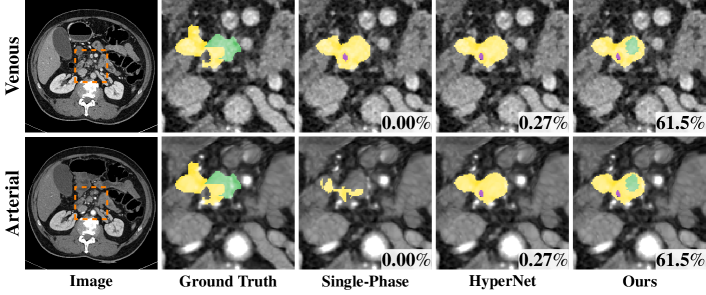

Refer to caption

Figure 4: Qualitative example where HPN detects the PDAC mass (green) while single-phase methods for both phases fail. From left to right: venous and arterial images (aligned), groundtruth, predictions of single-phase algorithms, HyperNet prediction, HPN prediction (overlayed with venous and arterial images). (Best viewed in color)

Another noteworthy fact is that 11/2391123911/239 cases are false negatives which failed to detect any PDAC mass using either phase (Dice = 0%percent00\%). Out of these 11 cases, 7 cases are successfully detected by HPN. An example is shown in Fig. 4 — the PDAC mass is missing from both single phases and almost missing in the original HyperNet (DSC=0.27%percent0.270.27\%), but our HPN can detect a reasonable portion of the PDAC mass (DSC=61.5%percent61.561.5\%).